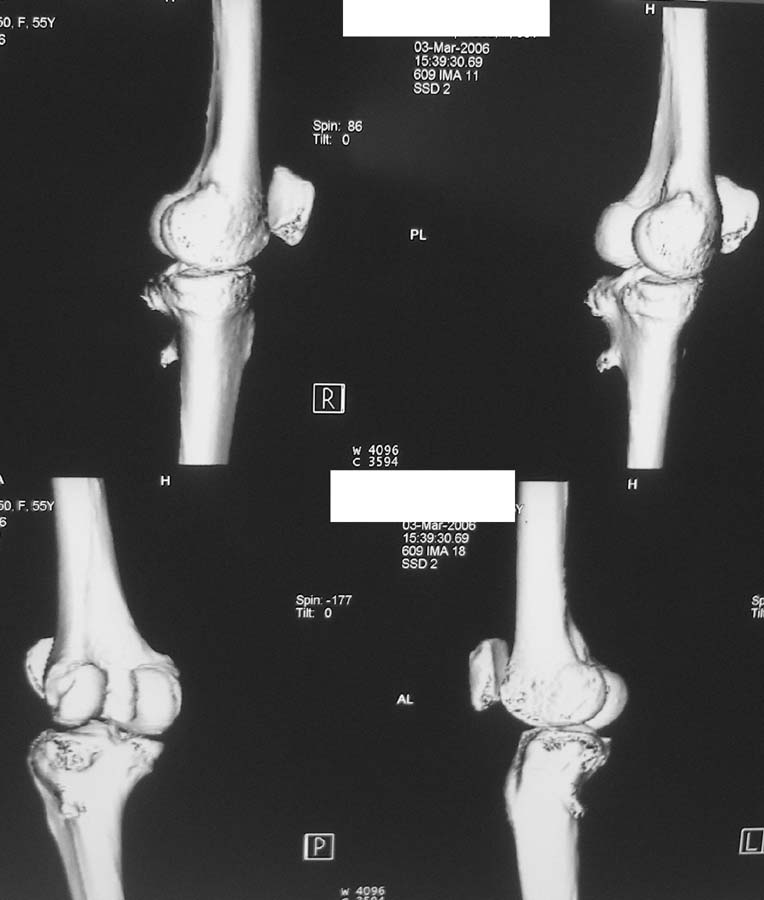

Женщина, 55 лет. С 2002 года - гонартроз. В настоящее время - боли в коленном суставе, стартовые боли, иногда в ночное время (проходит <от перемены положения ноги>).

Принимает НПВС, артрон-комплекс, внутрисуставно гиалган. Ревмопробы отрицательные. На рентгенограмме отметили сужение шейки малоберцовой кости, на спиральной КТ - экзостоз? Ваше мнение о целесообразности операции (велика вероятность повреждения нервов), предварительной биопсии? Спасибо!